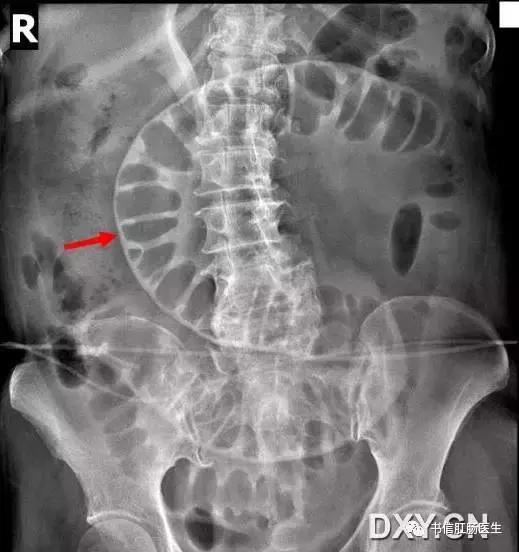

★ 气腹衬托下肠道外壁也可以清晰显示(红箭头)

■ 影像表现:在仰卧位腹部 X 线平片上,胃肠道腔内气体显示内壁的同时,气腹可将胃肠道外壁显示出来。

■ 征象解析:正常情况下气体仅显示肠壁内腔表面的轮廓而不显示浆膜表面,胃肠道外壁的密度类似邻近腹腔的内容物。而当腹腔内有适量的自由气体存在时,这些自由气体更可能集中在肠撵间,因此可以见到肠管的外壁,这就是双壁征的典型表现。当肠腔充满液体,内壁不可见,只有外侧壁是可见时,表现为不典型的双壁征。

■ 讨论:气腹的出现常提示病变严重,是急诊观察中应引起注意的征象,故认识其在常规的腹部 X 线平片表现非常重要。气腹常见的病因学有 4 种:医源性、自发性、外伤性和其他各种原因。气腹临床表现不特异,有的根本没有症状,也有的有明显的腹膜刺激征,因此详细询问病史很重要。

研究表明发现少量腹腔游离气体敏感的方法是腹部立位平片,能迅速发现膈下游离气体。对不能站立的患者,一种替代方法是左侧卧位,优质的侧卧位片与立位片一样,能发现 <1 ml 的腹腔游离气体。CT 能发现 1 ml 的游离气体,并帮助证实平片可疑的气腹。气腹有许多可能的平片表现,最普通的征象是右隔下游离气体,因为肝脏高密度轮廓的勾画使其表现比较明显。

双壁征有时能被邻近的肠襻干扰,因而在肠襻的内部也可出现相邻肠襻壁的轮廓,导致误诊为游离气体。腹部 CT 中少数剩余的增强剂覆盖在肠腔内表面也可增加肠壁密度形成假双壁征。对于不明确的病例,可通过左侧卧位照片或腹部立位片来证实。